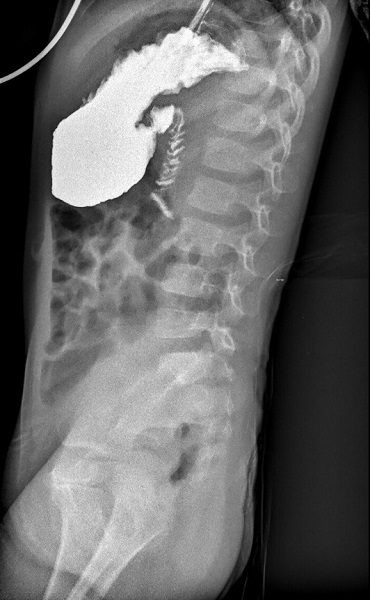

Se realiza posteriormente un TC abdominal (Figura 2) para completar información. Debido a que no se encuentra ninguna lesión que justifique el cuadro obstructivo (ni intrínseca ni extrínseca), se solicita una intervención quirúrgica urgente para la visualización abdominal mediante laparoscopia exploradora. En la intervención, se localiza una brida congénita yeyunal como causa de la obstrucción, que es resecada con éxito.

| Figura 2. TC abdominal. Atrapamiento duodenal con dilatación proximal. La brida no se visualiza como tal, pero sí su efecto compresivo |

Las pruebas de imagen utilizadas en estos casos, tales como la radiografía de abdomen, ecografía, tránsito digestivo superior y tomografía computarizada, normalmente objetivan datos inespecíficos compatibles con la obstrucción intestinal (dilatación de asas, niveles hidroaéreos), pero no suelen obtener una clara visualización directa de la propia brida. Por este motivo, el abordaje diagnóstico-terapéutico suele ser quirúrgico, más frecuentemente mediante laparoscopia exploradora, precisando en ocasiones una laparotomía1-4.